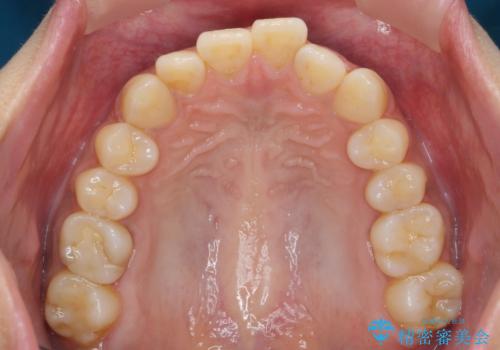

前歯のがたつきをすっきり マウスピース矯正

- 長年気になっていた前歯のがたつきをマウスピース矯正で治したい!と希望され来院されました。

奥歯の噛み合わせには問題がなく、前歯のがたつきの改善のみで十分に審美的な結果が得られるため、ワイヤーではなくマウスピース矯正での治療を計画します。

しっかりと前歯のがたつきは改善し見た目が大きく良くすることができました。